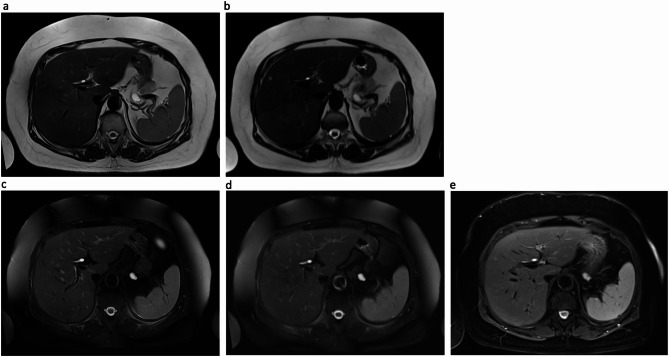

Materials and methods: DL-HASTE of the upper abdomen was acquired with variable sequence parameters regarding FS, flip angle (FA) and field of view (FOV) in 10 healthy volunteers and 50 patients. DL-HASTE sequences were compared to clinical sequences (HASTE, HASTE-FS and T2-TSE-FS BLADE). Two radiologists independently assessed the sequences regarding scores of overall image quality, delineation of abdominal organs, artifacts and fat saturation using a Likert scale (range: 1-5).

Results: Breath-hold time of DL-HASTE and DL-HASTE-FS was 21 ± 2 s with fixed FA and 20 ± 2 s with variable FA (p < 0.001), with no overall image quality difference (p > 0.05). DL-HASTE required a 10% larger FOV than DL-HASTE-FS to avoid aliasing artifacts from subcutaneous fat. Both DL-HASTE and DL-HASTE-FS had significantly higher overall image quality scores than standard HASTE acquisitions (DL-HASTE vs. HASTE: 4.8 ± 0.40 vs. 4.1 ± 0.50; DL-HASTE-FS vs. HASTE-FS: 4.6 ± 0.50 vs. 3.6 ± 0.60; p < 0.001). Compared to the T2-TSE-FS BLADE, DL-HASTE-FS provided higher overall image quality (4.6 ± 0.50 vs. 4.3 ± 0.63, p = 0.011). DL-HASTE achieved significant higher image quality (p = 0.006) and higher sharpness score of organs compared to DL-HASTE-FS (p < 0.001).

Conclusion: Deep learning-accelerated HASTE with and without fat saturation were both feasible at 3 Tesla and showed improved image quality compared to conventional sequences.